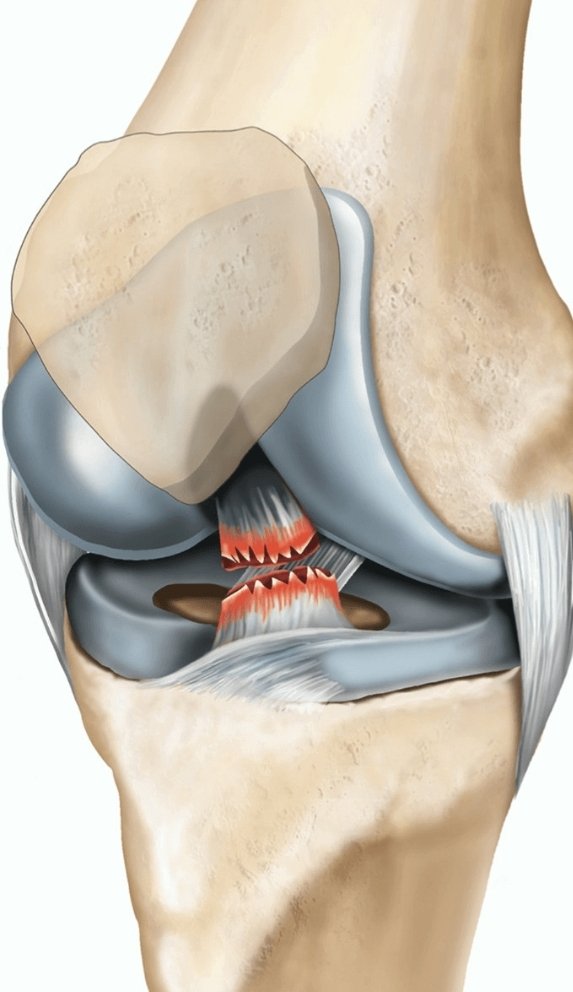

Hip fracture is considered a serious injury that can lead to impaired mobility, infection, bleeding, and other complications that pose risks to the patient. It is usually caused by falls or severe accidents. Examples of complications from hip fractures include:

Infections and wounds near the incision or injury site. Joint damage, as hip fractures can damage the cartilage surface of the joint. Injury to the sciatic nerve. If you would like to learn more about sciatic nerve injury and the development of sciatica, we recommend reading this article. The occurrence of something known as non-union, which is a rare problem. Anemia due to bone marrow damage. How Long Does Hip Fracture Recovery Take?